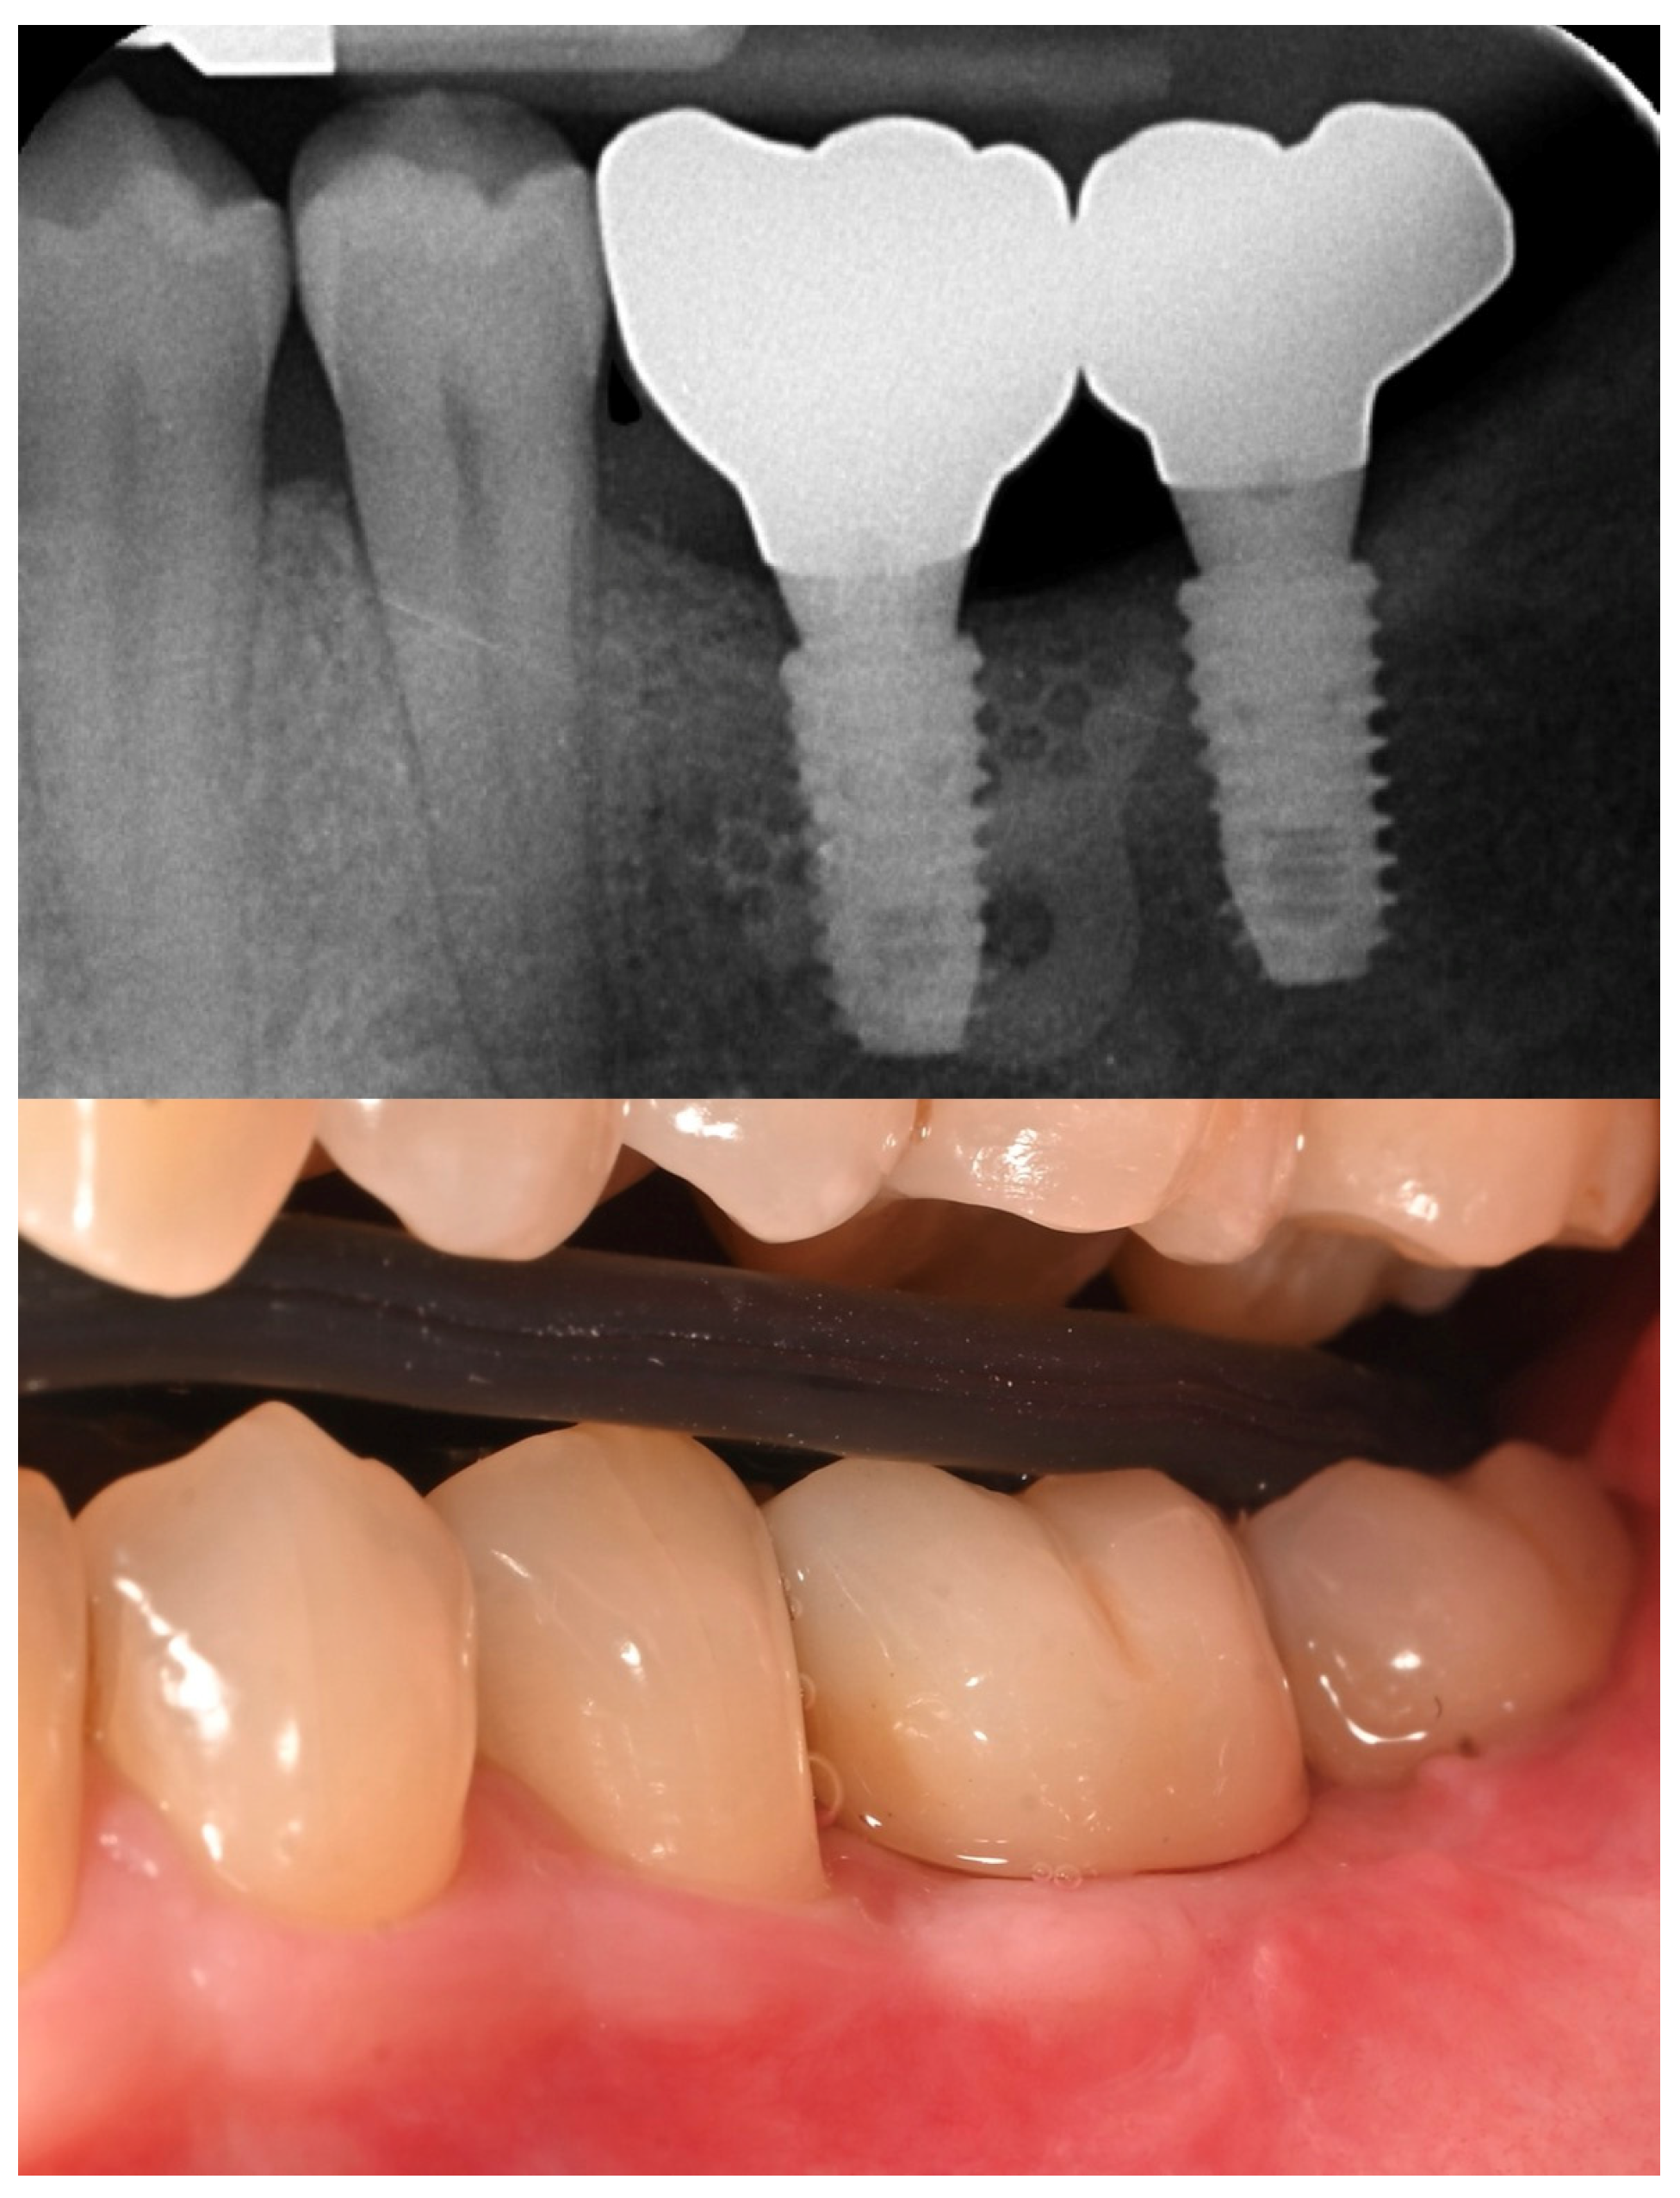

2. Case Summary